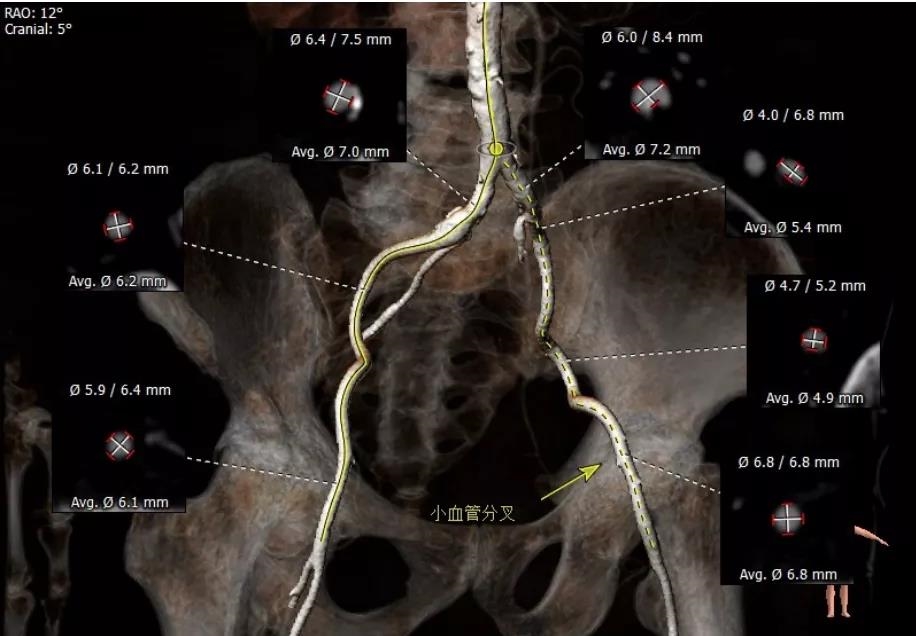

外周血管评估

术前经详尽影像学重建、评估及病例讨论,计划经右侧股动脉植入25#球扩式介入瓣。术中使用21#球囊进行预扩,植入25# Renatus®介入主动脉瓣。手术全程顺利,血流动力学稳定,主动脉瓣植入位置理想,功能表现出色,DSA及TEE评估无瓣中反流,仅有轻微瓣周反流。主动脉瓣峰值流速由术前4.4m/s降至1.6m/s,平均压差由术前49mmHg降至4.4mmHg。